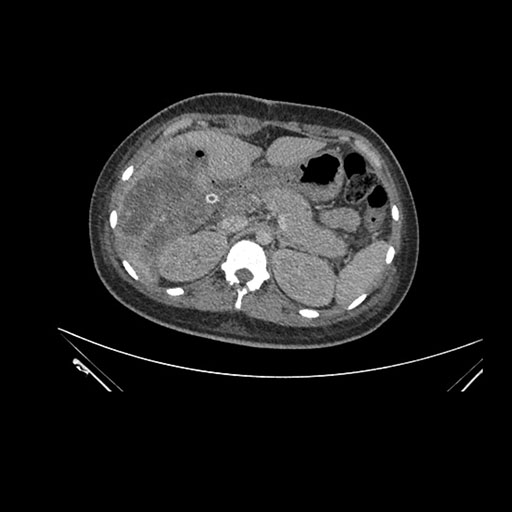

Imaging Analysis

Look through the patient's CT scan to identify any areas of concern for the necessary procedure.

Axial Venous

Based on initial findings, which issue(s) would you be most concerned about?